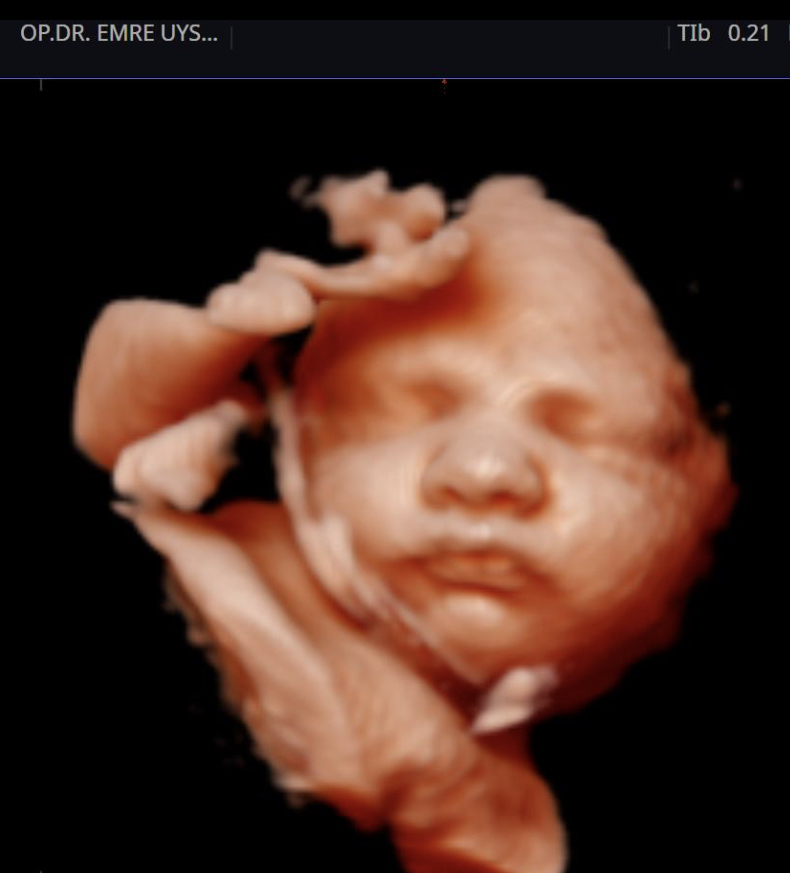

Her kadının hayatında önemli dönüm noktaları vardır. Hiç şüphesizki hamilelik süreci ve doğum bunlardan en kıymetlisidir. Biz de bu değerin farkındayız ve 15 yılı aşan tecrübemiz ile minik mucizenize sağlıkla kavuşma yolculuğunda sizin yanınızdayız. 4d ultrason ile bebeğinizin sağlığını yakından takip ederken, klinik takibimiz ile de süreci eğlenceli ve sağlıklı bir şekilde geçirmeniz için elimizden gelenin en iyisini yapıyor olacağız. Yaşasın Hamilesiniz!